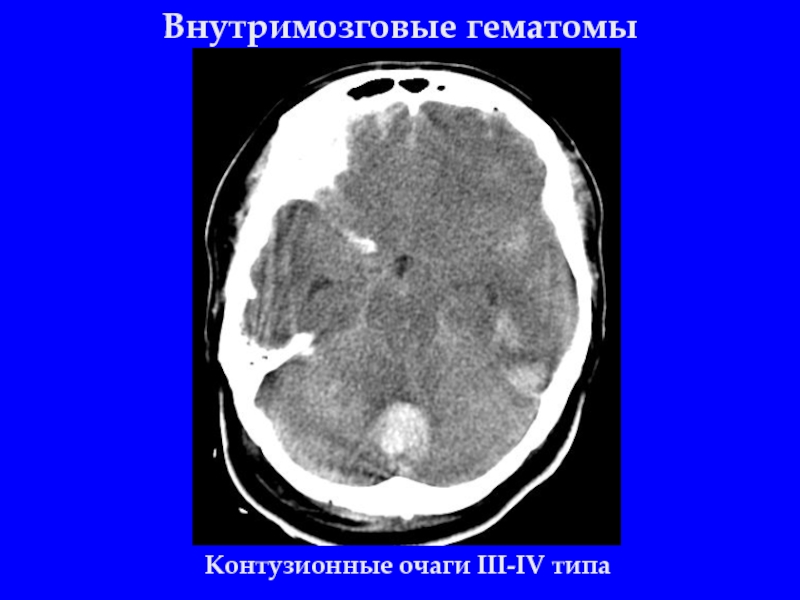

Слайд 22Внутримозговые гематомы

Контузионные очаги III-IV типа